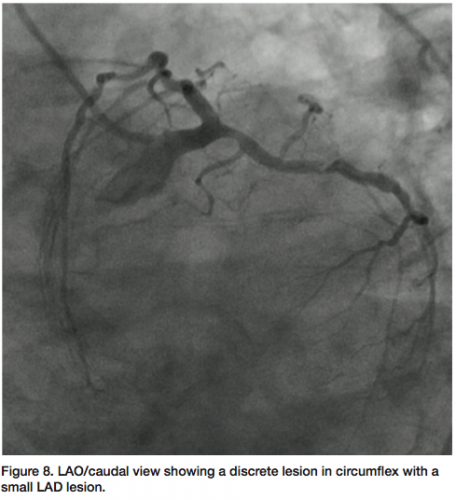

be totally occluded (probably chronic) (Figure 5) and a large posterior descending artery (PDA)/postero-lateral artery (PLA) system is noticed on angiography of the left arteries. The collaterals to the PDA/PLA appear to come from the left anterior descending coronary artery (LAD) and circumflex (Figure 6). The chronic total occlusion (CTO) appears moderate in length once the collateral and main vessels are visualized, with a calcific channel outlined.

The LAD shows “lumpidy-bumps,” but nothing more than a 70-80% (remember, it is subjective) lesion (Figure 7). There are smaller lesions throughout the artery. The circumflex has a lesion that could be repaired with angioplasty (Figure 8).